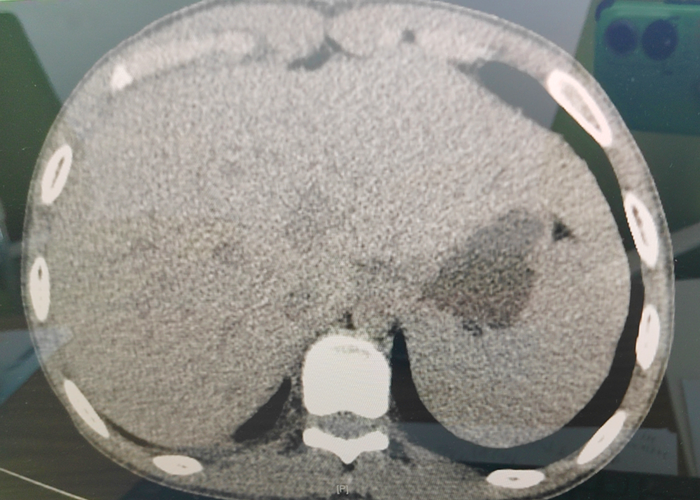

胸腹部增強(qiáng)CT造影等檢查

胸心普通外科主任吳新宇

憑借豐富經(jīng)驗及檢查結(jié)果

診斷為

腹部閉合傷

肝破裂

失血性休克